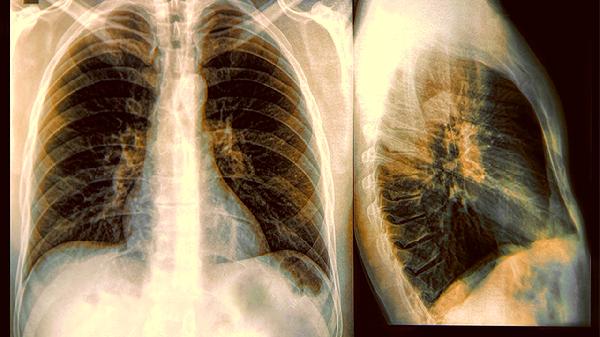

肺癌来临,睡觉就知?已经被肺癌找上门的人,睡觉会出现这3表现

肺癌早期往往没有明显症状,但睡眠时的某些异常可能是身体发出的警.报。如果你经常在睡觉时出现这些情况,建议及时就医检查。